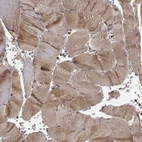

Immunohistochemical staining of human kidney shows moderate granular cytoplasmic positivity in cells in tubules.